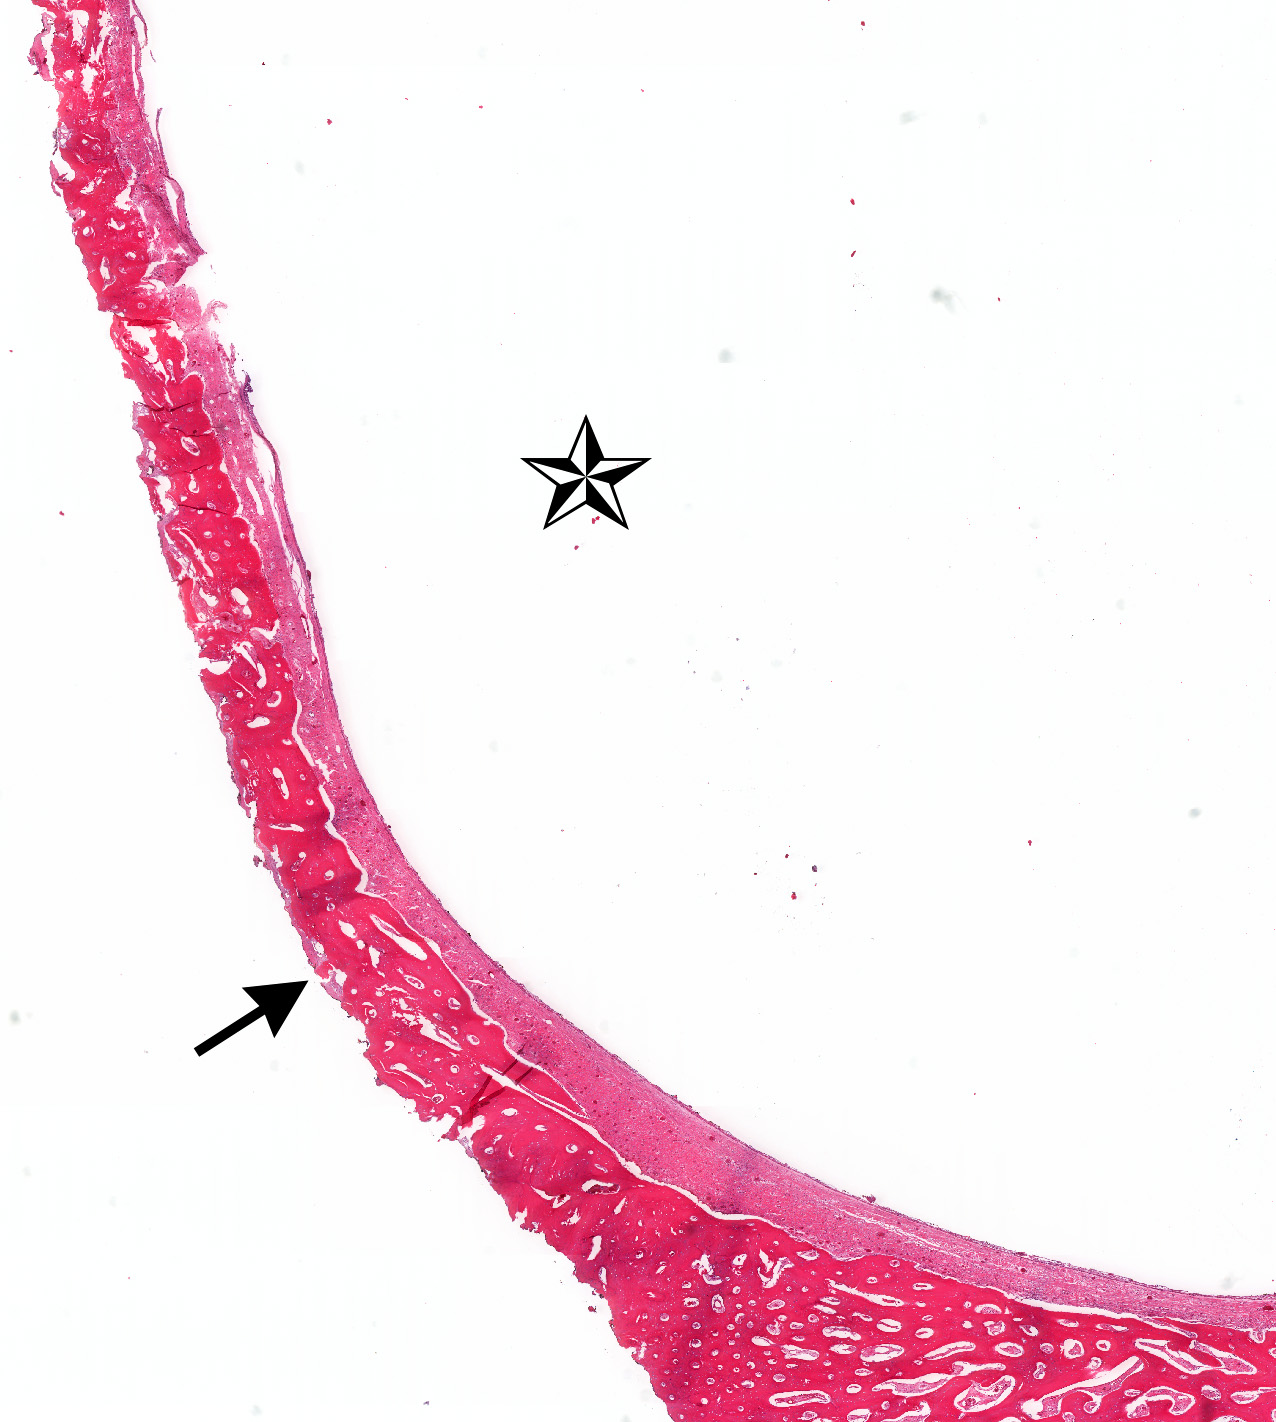

Microscopic (histologic) images

Contributed by Kelly Magliocca, D.D.S., M.P.H. and Anne C. McLean-Holden, D.M.D., M.S.

- Ameloblastoma, unicystic type has 3 histopathological patterns

- Single cystic lesion lined by ameloblastic epithelium that shows typical features of ameloblastoma in some areas, including columnar basal cells in palisading arrangement with vacuolated cytoplasm, hyperchromatic nuclei polarized away from basement membrane

- Suprabasal cells loosely textured and noncohesive resembling stellate reticulum, epithelial invagination, epithelial edema and separation

- Luminal: cystic odontgenic epithelium with characteristic features (above) lining fibrous connective tissue wall